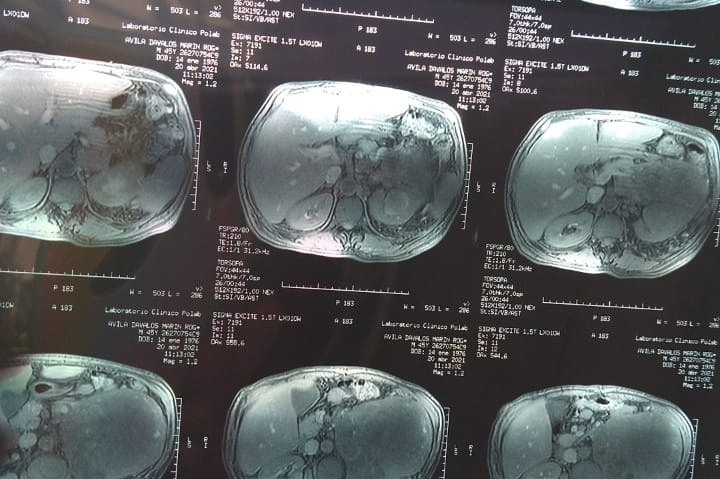

I never thought to do this but today I find myself in a very difficult situation. I want to be able to help my parents but I can't by myself. That is why my family and I ask for your help from the bottom of our hearts. My 55-year-old father with DM2 SAH (Type 2 Diabetes Mellitus and Hypertension) detected a large tumor two weeks ago that has been growing for many years. Known as Left Renal CA (Kidney Cancer) DX. My family and I have been going through very difficult times these past weeks since unfortunately we lost my Grandmother last month on April 14, 2021. A few weeks later we found out about the tumor that had been developing and forming in his body. Thanks to a fall he had and from which he began to shed blood, we decided to have him checked out because almost two years ago he had surgery to remove a hernia he had. When taking him to the clinic the Doctors decided to take tests to see what was going on in which his tumor was detected. Given the circumstances that we have gone through, my mother with the loss of my grandmother began to feel bad. So we also decided to take her to the doctor for a medical check-up in which they have also given us bad news since they have detected the development of a tumor in her throat and she also has symptoms of Diabetes. We are going through a very difficult and painful situation mentally and physically. We have had many medical expenses and there are many more expenses to come that we cannot afford like the surgery that my dad is going to need and the medical expenses that he and my mom will be faceing . We have seen several specialists with different opinions. But thank God we have found a doctor to operate on him on Monday May 10th, 2021. My family is a low-income family. That is why we are asking for your help to raise funds with all the medical expenses that my mom and dad will need. We have Faith in God and with the help of good people with you helping us with your prayers and donations we will be able to get through this difficult situation. Thank you very much and may GOD bless you and multiply you in every way.

Nunca pensé en hacer esto, pero hoy me encuentro en una situación muy difícil. Quiero poder ayudar a mis padres pero no puedo por mí misma. Es por eso que mi familia y yo pedimos su ayuda desde el fondo de nuestro corazón. Mi padre de 55 años con DM2 HAS (diabetes mellitus tipo 2 e hipertensión) detectó hace dos semanas un gran tumor que ha estado creciendo durante muchos años. Conocido como CA renal izquierdo (cáncer de riñón) DX. Mi familia y yo hemos pasado por momentos muy difíciles estas últimas semanas desde que lamentablemente perdimos a mi abuela el 14 de abril del 2021 el mes pasado. Unas semanas después nos enteramos del tumor que se había estado desarrollando y formándose en el cuerpo de mi papá. Gracias a una caída que tuvo y de la que empezó a derramar sangre, decidimos hacer que lo revisaran porque hace casi dos años lo operaron para extirpar una hernia que tenía. Al llevarlo a la clínica los médicos decidieron hacerle pruebas para ver qué estaba pasando en el que se detectó su tumor. Dadas las circunstancias por las que hemos pasado, mi madre con la pérdida de mi abuela empezó a sentirse mal. Así que también decidimos llevarla al médico para un chequeo médico en el que también nos han dado una mala noticia ya que han detectado el desarrollo de un tumor en su garganta y también tiene síntomas de Diabetes. Estamos atravesando una situación muy difícil y dolorosa mental y físicamente. Hemos tenido muchos gastos médicos y hay muchos más gastos por venir que no podemos afrontar, como la cirugía que va a necesitar mi papá y los gastos médicos que él y mi mamá tendrán que afrontar. Hemos visto a varios especialistas con opiniones diferentes. Pero gracias a Dios hemos encontrado un médico para operarlo el dia Lunes 10 de Mayo 2021. Mi familia es una familia de bajos ingresos. Por eso les pedimos su ayuda para recaudar fondos con todos los gastos médicos que necesitarán mi mamá y mi papá. Tenemos Fe en Dios y con la ayuda de buenas personas cono usted en ayudándonos con tus oraciones y donaciones podremos superar esta difícil situación. Muchas gracias y que DIOS te bendiga y te multiplique en todos los sentidos.